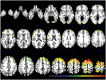

Objective: Exposure to ambient fine particulate matter (PM2.5: PM with aerodynamic diameters < 2.5 μm) has been linked with cognitive deficits in older adults. Using fine-grained voxel-wise analyses, we examined whether PM2.5 exposure also affects brain structure. Methods: Brain MRI data were obtained from 1365 women (aged 71-89) in the Women's Health Initiative Memory Study and local brain volumes were estimated using RAVENS (regional analysis of volumes in normalized space). Based on geocoded residential locations and air monitoring data from the U.S. Environmental Protection Agency, we employed a spatiotemporal model to estimate long-term (3-year average) exposure to ambient PM2.5 preceding MRI scans. Voxel-wise linear regression models were fit separately to gray matter (GM) and white matter (WM) maps to analyze associations between brain structure and PM2.5 exposure, with adjustment for potential confounders. Results: Increased PM2.5 exposure was associated with smaller volumes in both cortical GM and subcortical WM areas. For GM, associations were clustered in the bilateral superior, middle, and medial frontal gyri. For WM, the largest clusters were in the frontal lobe, with smaller clusters in the temporal, parietal, and occipital lobes. No statistically significant associations were observed between PM2.5 exposure and hippocampal volumes. Conclusions: Long-term PM2.5 exposures may accelerate loss of both GM and WM in older women. While our previous work linked smaller WM volumes to PM2.5, this is the first neuroimaging study reporting associations between air pollution exposure and smaller volumes of cortical GM. Our data support the hypothesized synaptic neurotoxicity of airborne particles.